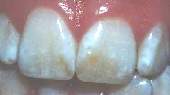

Dental fluorosis is now pandemic in fluoridated areas. Fluoride ingestion in children is clearly out of control given the sky-rocketing rise in fluorosis rates in fluoridated communities. Developed nations with fluoridated comunities have some of the highest rates in the world.

DENTAL FLUOROSIS, recognized by scientists world-wide as the first clinical sign

of fluoride poisoning. The fluoride also attacks your entire skeletal bone system